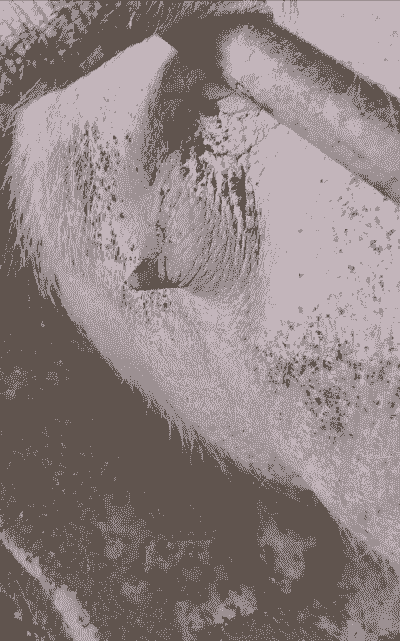

如果恶露颜色出现异常,可能表明母猪存在某种健康问题。以下是一些常见的异常颜色及其可能的原因:

黑色:

可能表示恶露中混有血液或其他有机物,提示可能有炎症或感染。

红色:

恶露中带有红色,可能表示有新鲜出血,提示可能有子宫内膜炎或其他严重炎症。

棕色:

可能是血液在子宫内停留时间较长,经过一段时间后变色。

黄色:

黄色恶露可能表示有较多的白细胞和细菌,提示可能有感染。